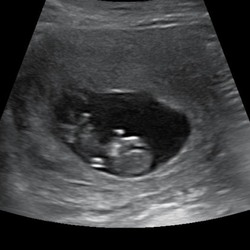

Ik dacht dat je dit beter kon vermijden tijdens de zwangerschap. Zowel gewo ...

Alleen de Vega pate wordt afgeraden ivm listeria bacterie maar ZwangerHap keurt het goed 🤷🏻♀️